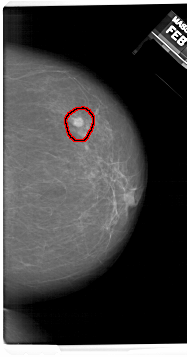

A_1409_1.RIGHT_CC

RIGHT_CC LINES 6766 PIXELS_PER_LINE 3541 BITS_PER_PIXEL 12 RESOLUTION 43.5 OVERLAY

FILE: A_1409_1.RIGHT_CC.OVERLAY

TOTAL_ABNORMALITIES 1

ABNORMALITY 1

LESION_TYPE MASS SHAPE ROUND MARGINS ILL_DEFINED

ASSESSMENT 4

SUBTLETY 4

PATHOLOGY BENIGN

TOTAL_OUTLINES 1

BOUNDARY